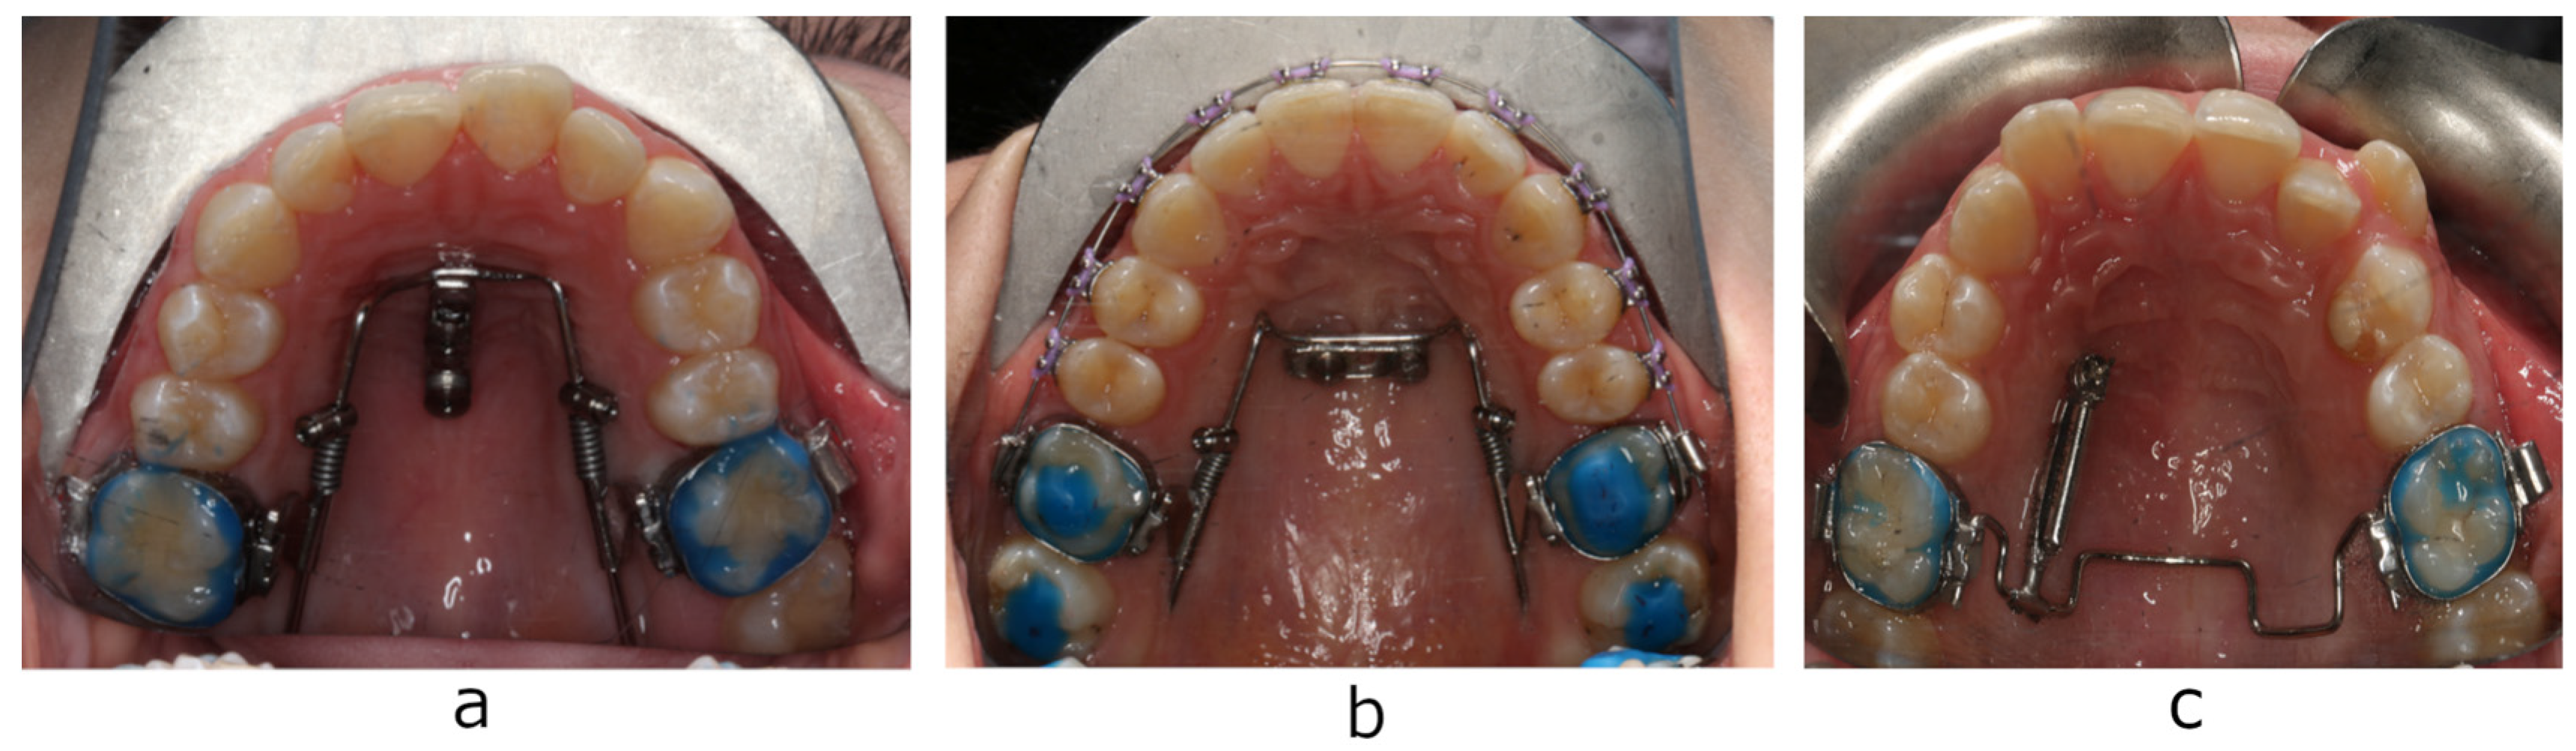

The aim of the present study was to evaluate palatal soft and hard tissue thickness using cone beam computed tomography (CBCT) at the area of micro-implant placement of two appliances for maxillary first molar distalization, that are successfully used in the Department of Prosthodontic and Orthodontics of Jagiellonian University in Cracow: Beneslider (PSM Medical Solutions, Tuttlingen, Germany) and TopJet distalizer (Tiger Dental, Bregenz, Austria) (Figure 1 and Figure 2).

Figure 1.

Bone-anchored distalizers: (a) Beneslider distalizer with mini-implants positioned medially; (b) Beneslider distalizer with mini-implants positioned paramedially; (c) TopJet distalizer.

Beneslider is a distalization appliance supported with two orthodontic mini-implants (7, 9, or 11 mm long) positioned medially or paramedially in the anterior palate [2,3]. The TopJet distalizer is a prefabricated appliance anchored by a single miniscrew (10, 12, or 14 mm long) in the anterior palate, laterally to the midpalatal suture [4]. Although cortical bone thickness determines the primary stability of micro-implants [5,9,10], it is essential to know total bone and soft tissue thickness to choose the appropriate implant length. In light of this fact and the lack of studies comparing implantation conditions for these two popular distalizers, the present study was carried out to provide clinically relevant information allowing to choose an adequate distalization system. Additionally, thus far, no studies have been conducted in the Polish population to assess palatal bone thickness. The hypothesis of the present study was that the palatal bone and mucosa thickness tends to increase from medial to lateral regions and decrease from anterior to posterior areas of the hard palate. Since both young and adult patients are seeking orthodontic treatment, another objective was to evaluate dependency between bone availability, age, and gender.